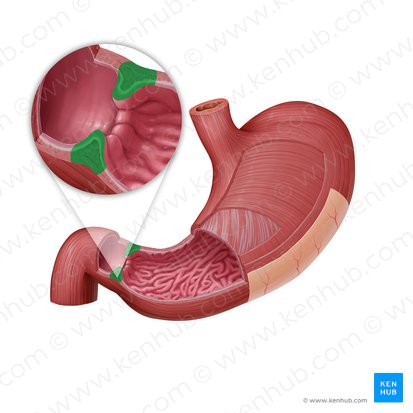

Lower esophageal sphincter

A muscular ring located at the junction of the esophagus and the stomach that controls the passage of food into the stomach and prevents reflux of stomach contents back into the esophagus

Cardia

The region of the stomach where the esophagus joins.